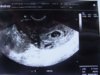

na razie jest puste jajo, wg usg to dopiero 5 tyczień i 1 dzień... a nie tak jak wg om 5 tydz i 4 dzień czekamy tydzień...

Chyba wszystko widać - ciałko żółte u góry, na dole zaznaczony Dzidziuch